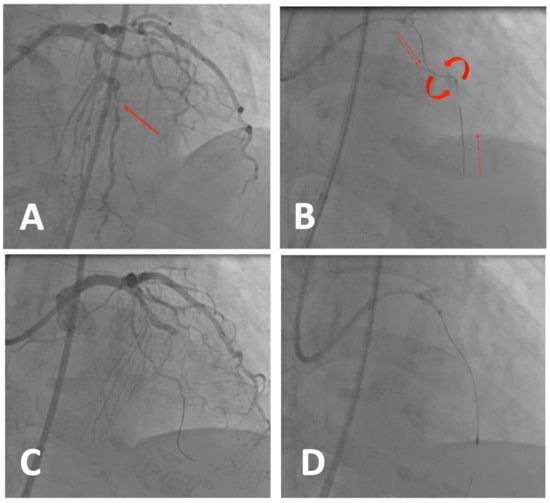

5.4. Case 3